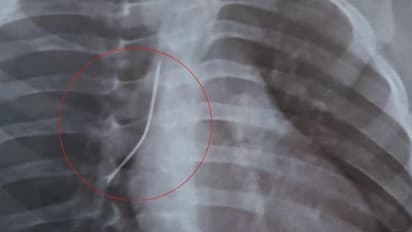

കൊച്ചി: ഒരു വയസ് മാത്രം പ്രായമുള്ള കുഞ്ഞിന്റെ ശ്വാസനാളത്തിൽ നിന്ന് 4 സെന്റീമീറ്റർ നീളമുള്ള സേഫ്റ്റി പിൻ പുറത്തെടുത്തു. എറണാകുളം വിപിഎസ് ലേക്ഷോർ ആശുപത്രിയിൽ നടത്തിയ ബ്രോങ്കോസ്കോപിയിലൂടെയാണ് പിൻ പുറത്തെടുത്തത്. ശ്വാസമെടുക്കാൻ കടുത്ത ബുദ്ധിമുട്ട് അനുഭവപ്പെട്ടതിനെ തുടർന്ന് അത്യാഹിത വിഭാഗത്തിലെത്തിച്ച കുട്ടിയുടെ ശ്വാസനാളത്തിൽ എക്സേറേ പരിശോധനയിലാണ് പിൻ കണ്ടെത്തിയത്.

അതീവ അപകട സാധ്യത കണക്കിലെടുത്ത് അടിയന്തിരമായി ബ്രോങ്കോസ്കോപ്പിക്ക് കുട്ടിയെ വിധേയമാക്കി. വിപിഎസ് ലേക്ഷോറിലെ പൾമണറി ക്രിട്ടിക്കൽ കെയർ & സ്ലീപ്പ് മെഡിസിൻ വകുപ്പിലെ കൺസൾട്ടന്റായ ഡോ. മുജീബ് റഹ്മാന്റെ നേതൃത്വത്തിലാണ് ബ്രോങ്കോസ്കോപി നടത്തിയത്. കുട്ടി ഇപ്പോൾ സുഖം പ്രാപിക്കുന്നതായാണ് ആശുപത്രി അധികൃതർ അറിയിക്കുന്നത്.

കഴിഞ്ഞ ദിവസം വീട്ടിൽ കളിച്ചുകൊണ്ടിരിക്കെയാണ് വസ്ത്രം തൈക്കുമ്പോൾ ഉപയോഗിക്കുന്ന പിൻ കുഞ്ഞ് വായിലിട്ടത്. ശ്വാസ തടസം അനുഭവപ്പെട്ടതോടെ കുഞ്ഞിനെ വീട്ടുകാർ ആശുപത്രിയിലെത്തിക്കുകയായിരുന്നു. കുഞ്ഞിൻ്റെ പേര് വിവരങ്ങൾ ആശുപത്രി അധികൃതർ പുറത്തുവിട്ടിട്ടില്ല.